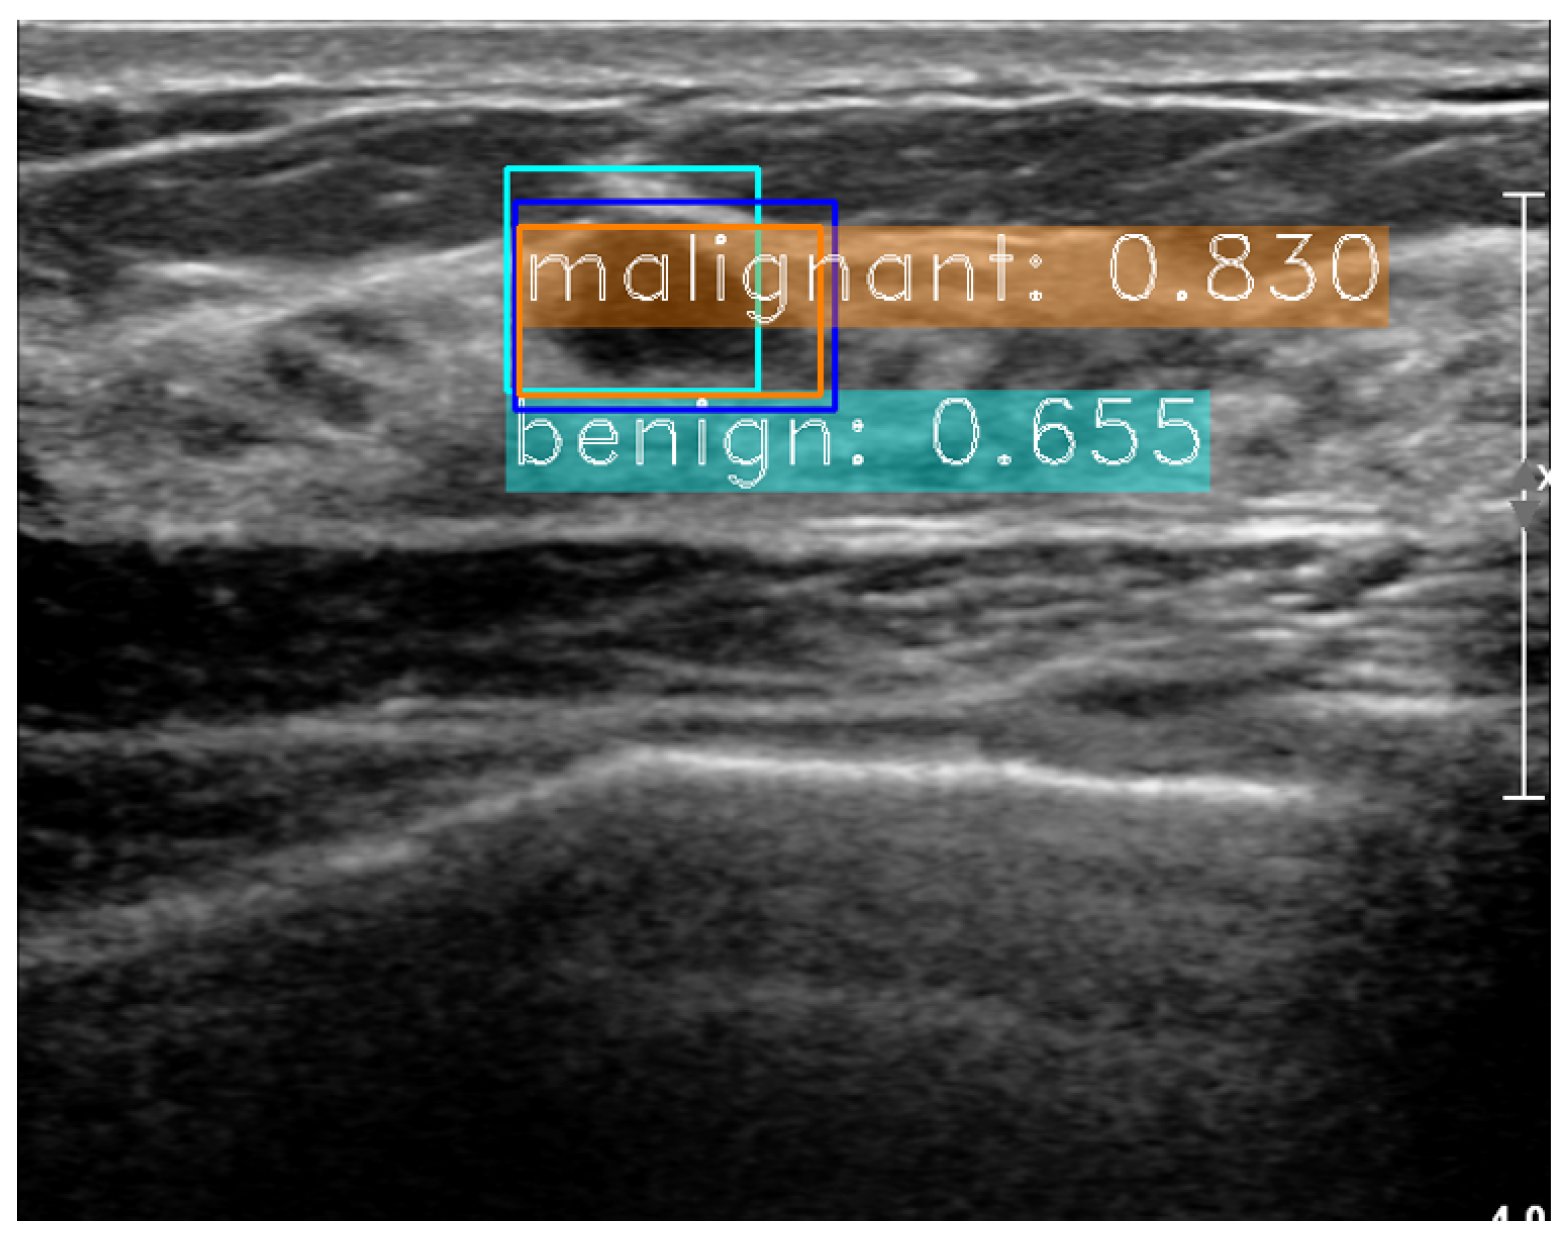

2.4. Dactive Construction with Dweak Test Results

3.3. Experiments for Active Learning on SNUBH Dataset

3.4. Experiments on Comparable Object Detectors